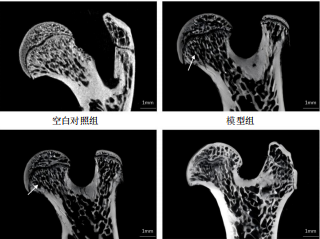

METHODS: Thirty-two Sprague-Dawley rats were randomly assigned to four groups: blank control, model, low-dose Gugutou Huaisiyu Capsule, and high-dose Gugutou Huaisiyu Capsule groups with eight rats in each group. Steroid-induced femoral head necrosis rat models were established via intraperitoneal injection of lipopolysaccharide combined with gluteal injection of methylprednisolone in the later three groups. Seven days post-modeling, rats in the low- and high-dose Gugutou Huaisiyu Capsule groups received intragastric administration of 0.33 g/kg and 0.67 g/kg of the decoction, respectively, while the blank control and model groups received intragastric administration of saline once daily for 8 consecutive weeks. Following the final administration, trabecular bone microarchitecture in the femoral head was assessed using micro-CT analysis. The mechanical pain thresholds were measured with the Von Frey test. Serum levels of pain mediators calcitonin gene-related peptide and substance P were detected using ELISA. Multiplex immunofluorescence staining and real-time quantitative PCR were used to detect the protein and gene expression of tyrosine kinase receptor A, calcitonin gene-related peptide, and neuronal marker β3-tubulin in the femoral head and dorsal root ganglion.

RESULTS AND CONCLUSION: (1) Micro-CT and pain behavioral tests revealed that compared with the blank control group, significant destruction of trabecular bone microarchitecture in the femoral head, decreased bone density and bone volume fraction, increased trabecular separation, and reduced mechanical pain threshold are found in the model group. Compared with the model group, trabecular structure significantly improved, bone mineral density and bone volume fraction significantly increased, trabecular separation significantly decreased, and mechanical pain threshold significantly elevated in the low- and high-dose Gugutou Huaisiyu Capsule groups. (2) ELISA analysis revealed calcitonin gene-related peptide and substance P levels were significantly increased in the model group compared with the blank control group, while calcitonin gene-related peptide and substance P levels were significantly decreased in the low- and high-dose Gugutou Huaisiyu Capsule groups compared with the model group. (3) Multiplex immunofluorescence staining and real-time quantitative PCR revealed that compared with the blank control group, protein and gene expression of calcitonin gene-related peptide, tyrosine kinase receptor A, and β3-tubulin were significantly elevated in the femoral head and dorsal root ganglion in the model group. Compared with the model group, protein and gene expression of calcitonin gene-related peptide, tyrosine kinase receptor A, and β3-tubulin were significantly decreased in the femoral head and dorsal root ganglion in both low- and high-dose Gugutou Huaisiyu Capsule groups. (4)The findings suggest that Gugutou Huaisiyu Capsule can elevate the mechanical pain threshold, suppress abnormal neuronal activation, and alleviate pain sensitization in rats with steroid-induced osteonecrosis of the femoral head. This mechanism may involve the inhibition of tyrosine kinase receptor A.